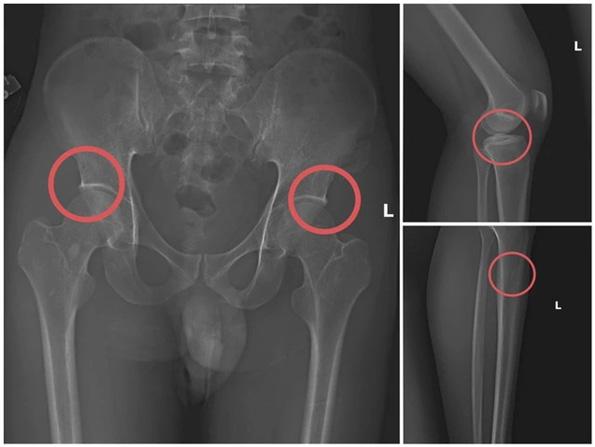

고의로 뼈를 부러뜨려 보험금 6억 동을 편취…푸토 지방경찰, 조직적 보험사기

푸토성 공안은 생명보험에 가입한 뒤

스스로 뼈를 골절시키는 방식으로 부

상을 위조해 약 60억 동의 보험금을

편취한 조직적 보험사기단을 적발했

다고 11월 14일 밝혔다.

푸토성 공안청 형사수사국은 긴급체 포 영장을 집행해 타 민 쪼우(30세,

전 껌케 현 의료센터 직원)를 비롯해

호앙 반 찌엉, 호앙 반 탕, 호앙 티 홍

디엡, 응우옌 아잉 줌 등 5명을 긴급

체포하고, 사건 연루자 6명도 추가로

임시 구금해 조사 중이라고 전했다.

이 중 쪼우가 범행을 기획하고 조직

을 이끈 핵심 인물로 확인됐다.

수사 결과, 의료 분야에서 오래 근무

고액 보험금이 책정되는 특정 뼈 부

위를 정확히 노려 골절을 유발해 보

험사의 이상 징후 탐지조차 어렵게

만들었다는 점이 확인됐다.

이 조직은 Manulife, AIA, Dai-ichi

Life, FWD, Sun Life, Chubb Life

등 다수의 생명보험회사로부터 총

60억 동 이상을 부당 수령했으며, 그

중 Manulife가 약 26억 동을 피해

본 것으로 조사됐다.

하며 골·관절 구조와 보험사 손해사

정 기준을 잘 알고 있던 쪼우는, 높은

보험금이 책정되는 골절 부위를 노린

범죄 절차를 체계적으로 설계한 것

으로 드러났다. 그는 보험 가입을 유

도하고, 직접 마취제를 투여한 뒤 주

사기 바늘과 못망치 등을 이용해 피

해자 신분의 공범들에게 골절을 유발

해 실제 사고와 유사한 손상을 만들

어냈다.